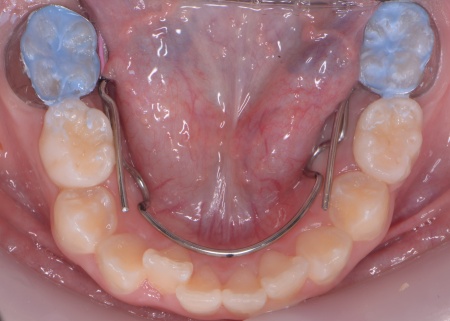

まず、上顎に顎の骨を広げるための固定式の矯正器具「急速拡大装置」を、下顎には歯並びの幅を広げるための「リンガルアーチ」を装着します。

治療を進めた結果、上顎は約6mm拡大し、歯が並ぶためのスペースを確保することができました。

次に歯の位置を整えるため、ワイヤー矯正を開始します。

上前歯6本と左右の奥歯の表面に「ブラケット」と呼ばれるボタン状の装置を設置し、そこにワイヤーを通して歯を少しずつ動かしていきました。

この装置は、歯の高さや位置のばらつきを整える「レベリング」を行うためのもので、拡大によって確保したスペースを活かしながら、歯並びを段階的に整えます。